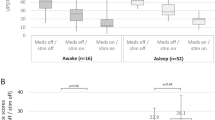

The operating room time, defined as skin-to-skin contact time, for 97 bilateral implantation procedures is 139.3 ± 34.7 min. For 11 unilateral implantations, the operating room time is 115.4 ± 42.1 min. Operating time was not available for the remaining 20 procedures.